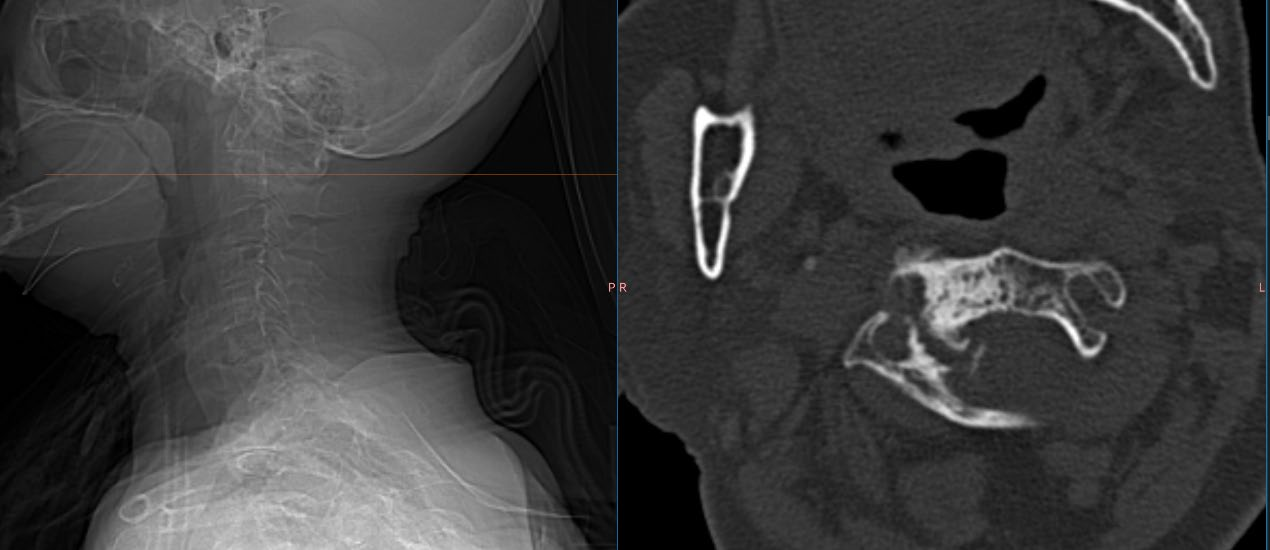

3月12日,疼痛科王立奎和陈家骅教授团队成功完成了一例老年患者的寰椎(第一颈椎)骨水泥注射术。患者为 80 岁女性,因“颈枕部疼痛8月加重2月余”就诊于我院疼痛科。患者表现为抬头后右侧后枕部疼痛明显。该患者每次下地活动20分钟后就必须平卧,正常生活起居受到极大影响。经检查患者系寰椎存在血管瘤占位,累及整个右侧寰椎侧块。

在完善相关检查后,团队采用自制的骨水泥注射针,在CT导航下完成了患者的寰椎骨水泥注射成形术。术后在王春霞护士长的护理团队的配合下,目前患者症状明显缓解,正常生活起居不再受限。患者对科室的治疗护理非常满意。

王立奎主任表示,由于颈椎的解剖结构复杂,周围毗邻颈脊髓及重要血管、气道及消化道等,骨水泥注射成形术难度大且并发症发生率相对较高。因此颈椎椎体成形术开展相对较少,而由于第一颈椎解剖及其位置的特殊性,此类手术更是鲜有报道。

颈椎的骨水泥注射对椎体成形术技术和手术精细程度都有极高的要求。科室以往已经成功实施了数十例的颈椎该类型手术,但以往主要是第二颈椎以下的椎体。据了解,本例C1骨水泥注射应该属于省内第一例,这也标志着科室目前可以完成全脊柱所有椎体的骨水泥成形术,达到了国内领先水平。

我院疼痛科自 2000 年开展该项技术以来,累计完成近3000例该类手术。与传统技术不同的是,科室采用的是CT导航下穿刺,能更清晰地显示椎体周围解剖结构,轴位成像使得上胸椎及颈椎的穿刺更具安全性和准确性。手术在局部麻醉方式下进行,对患者年龄及身体一般情况要求相对较低。且因为CT导航的精确性,骨水泥可精准注射到病变靶点,从而更安全更高效的解决患者不适症状。